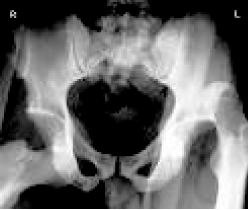

患者,女性,32岁,已婚,农民,因车祸后右髋部疼痛不能活动2小时入院。患者于2小时前因乘车时汽车紧急刹车,右膝部撞击前面座位,立即感到右髋部疼痛、不能站立及活动,被送来本院。入科时查体:患者神志清醒,痛苦面容,营养良好,微胖体型,全身皮肤黏膜无黄染,右髋部肿胀、压痛,可触及脱出股骨头,右下肢呈屈曲内收内旋畸形,右髋关节呈弹性固定,右下肢末梢血运感觉可。辅助检查:X线检查示右髋关节后脱位。诊断为右髋关节后脱位。

患者X线检查